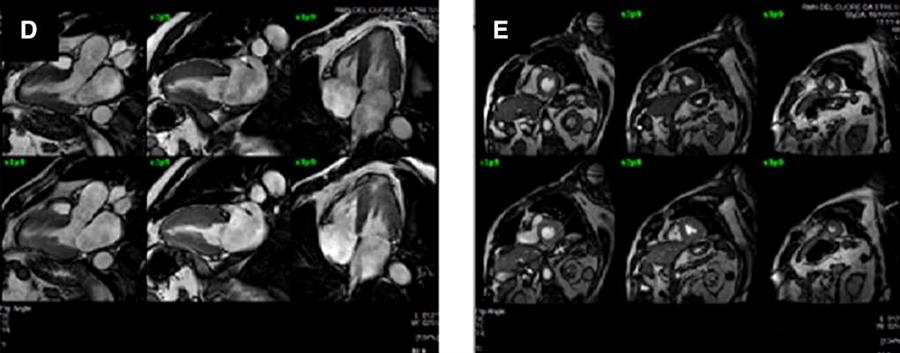

Una successiva valutazione con stress-RM (D,E) non ha però mostrato difetti di perfusione né anormalità delle pareti vasali. E durante il follow-up non sono intervenuti eventi cardiovascolari maggiori.